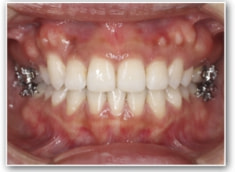

治療法:裏側の矯正(リンガルブラケット:舌側矯正)

治療後